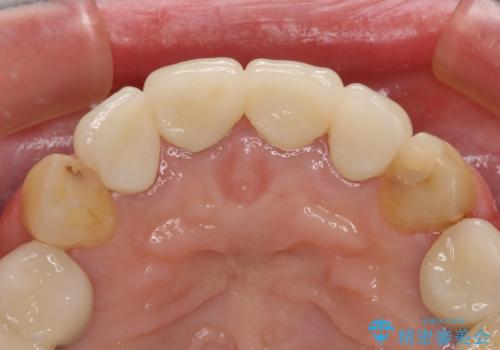

日頃の歯磨きをしっかりと行ってくださるので、新しい仮歯に変えてから速やかに歯肉の状態が改善されました。

歯肉からの出血がほとんどないため精度の良い型取りができ、非常に適合の良い補綴治療を行うことができました。